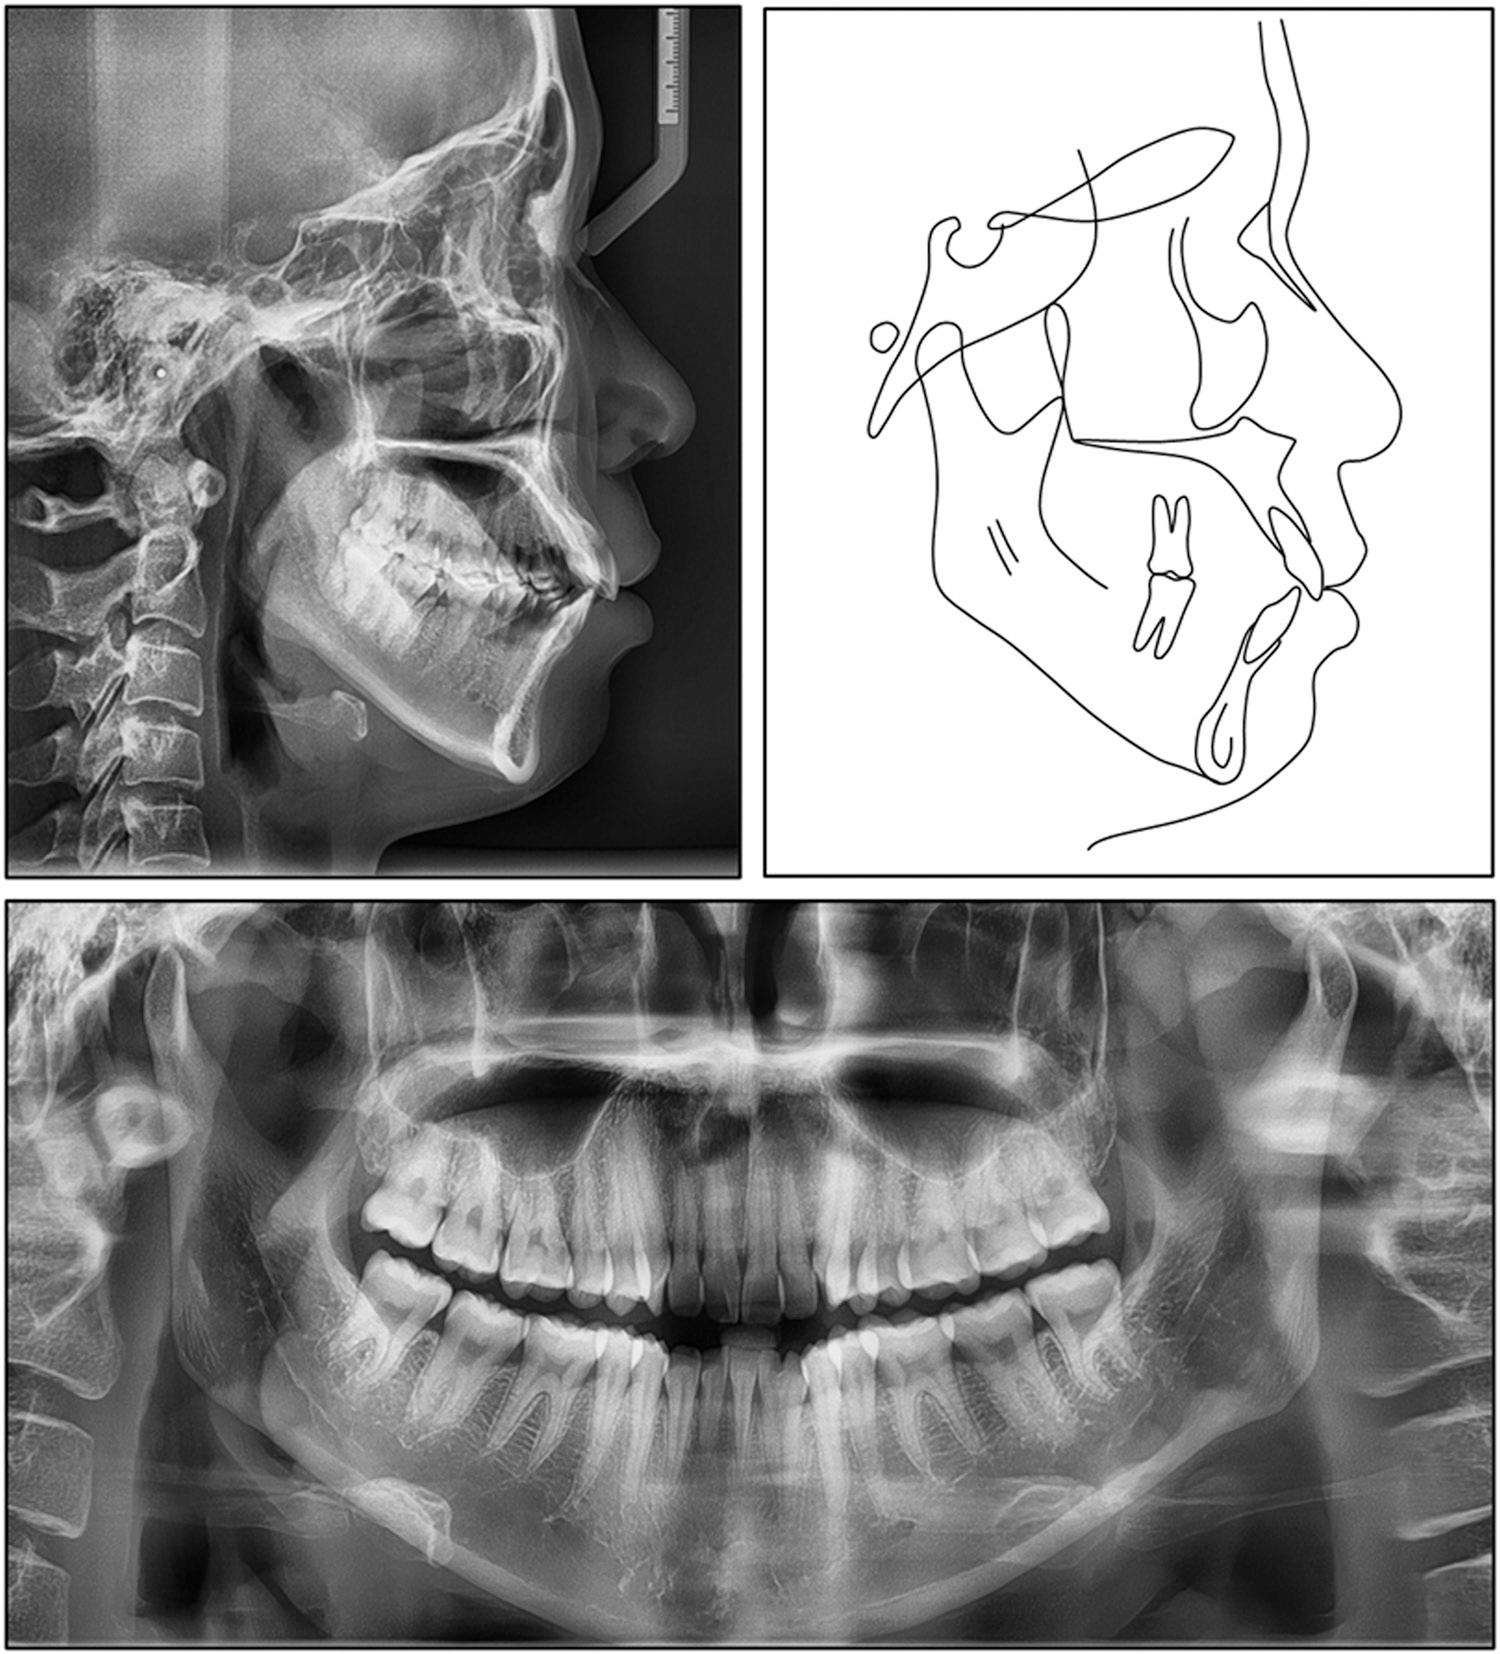

During the second year of treatment, heavier rectangular wires (0.021 × 0.025-inch NiTi and stainless steel) were introduced for final detailing and torque control. In the finishing stage, vertical elastics were applied to settle the occlusion. Plans for future laminate veneers were co-ordinated during this phase, and the space between the left fused unit and adjacent teeth was managed to accommodate this restorative procedure (Figure 4).

Clinical photographs after 13 months of treatment.